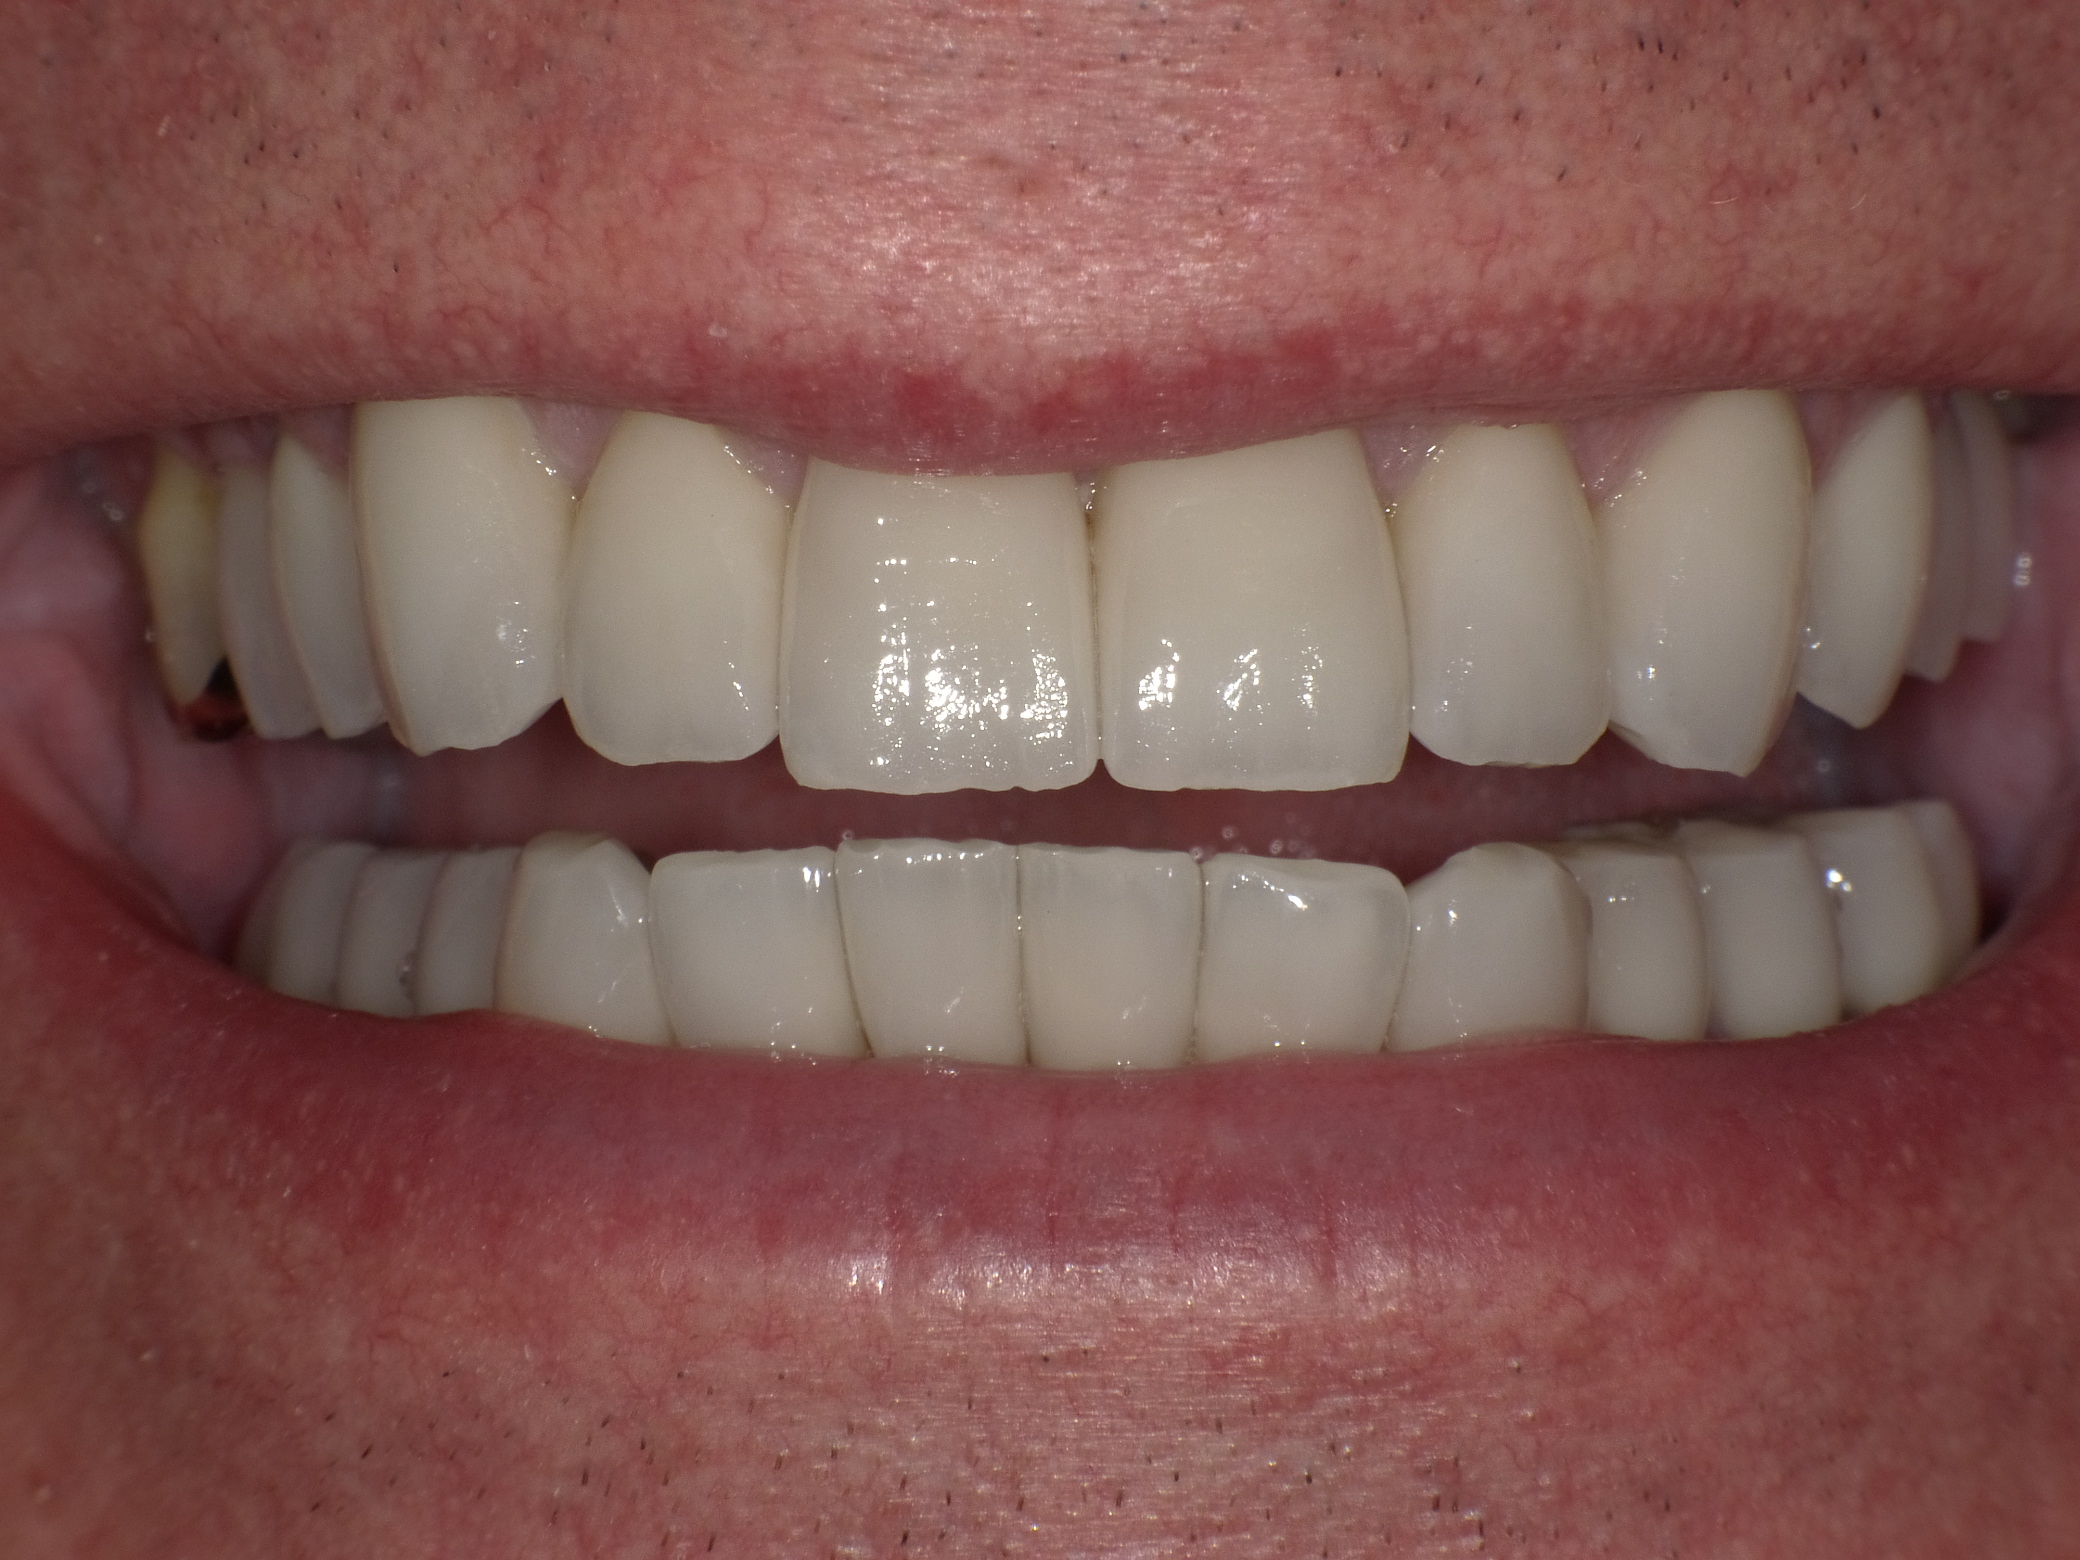

gescheiterte Implantat-Versuche und künstlich aussehende, leblose Kronen

Vorher: gescheiterte Implantat-Versuche und künstlich aussehende, leblose Kronen

Strahlende Vollkeramik-Kronen; unten festsitzende Kronen auf neu gesetzten Implantaten

Nachher: Strahlende Vollkeramik-Kronen; unten festsitzende Kronen auf neu gesetzten Implantaten